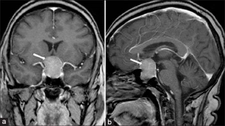

Hipofiz Ameliyatı Nasıldır?Hipofiz ameliyatı, hipofiz bezinin hastalıklarının tedavisi amacıyla yapılan cerrahi bir işlemdir. Hipofiz bezi, beynin altında yer alan ve hormon salınımını düzenleyen küçük bir bezdir. Bu bezin işlev bozuklukları, çeşitli sağlık sorunlarına yol açabilir. Bu makalede, hipofiz ameliyatının nasıl gerçekleştirildiği, süreçleri ve dikkat edilmesi gereken noktaları ele alacağız. Hipofiz Bezi ve ÖnemiHipofiz bezi, vücut hormonlarının düzenlenmesinde kritik bir rol oynar. Aşağıdaki işlevleri vardır:

Hipofiz bezinde tümörler veya diğer patolojik durumlar, bu hormonların dengesini bozarak çeşitli sağlık sorunlarına neden olabilir. Hipofiz Ameliyatının NedenleriHipofiz ameliyatı genellikle aşağıdaki durumlar için yapılır: